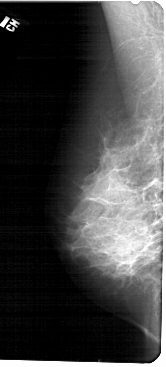

A_1682_1.RIGHT_MLO

RIGHT_MLO LINES 5491 PIXELS_PER_LINE 2236 BITS_PER_PIXEL 12 RESOLUTION 43.5 OVERLAY